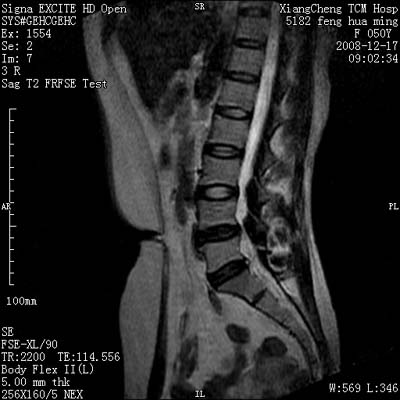

患者,女,50岁,左侧腹股沟及其下方疼痛、酸沉2年。

请各位战友看一下l4-5椎间盘后方椎管内是病灶吗?马尾神经到此处是不是终止了?

l4/5椎间盘突出。后方硬膜囊受压改变。另外,该病人是否并发子宫肌瘤啊

腰椎各椎间盘有不同程度的突出.

腰45椎间盘突出,马尾终丝聚集:考虑蛛网膜炎症粘连

l4-5轻突,黄韧带增厚,蛛网膜炎症粘连可能

l4/5椎间盘突出;马尾终丝聚集,考虑蛛网膜炎所致。